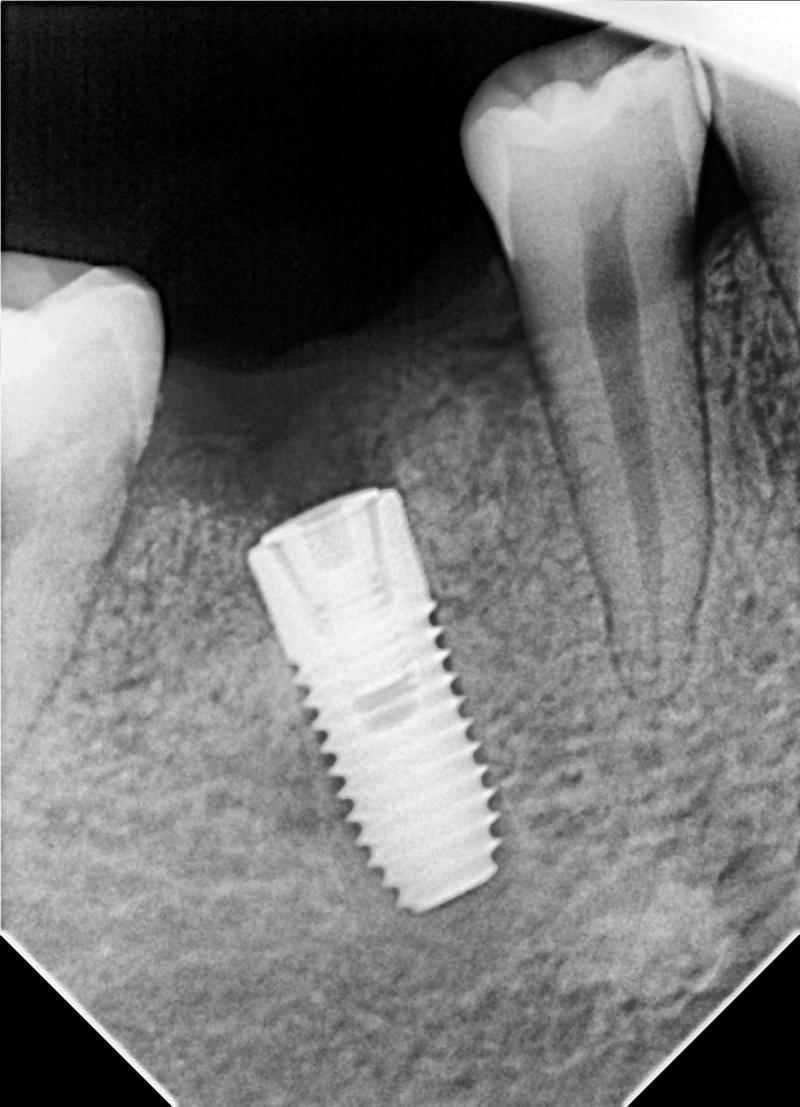

Nha Khoa Bs Hùng

Khi đến với Nha Khoa Bs Hùng, bạn sẽ được làm các dịch vụ nha khoa với công nghệ, phương pháp tiên tiến nhất hiện nay. Khi đến trồng răng tại đây, bạn không những được tư vấn một cách chi tiết nhất về quá trình điều trị mà còn được làm bởi các bác sĩ có kinh nghiệm lâu năm trong nghề.

Những ưu điểm khi trồng răng implant tại Nha Khoa Bs Hùng:

- Bác sĩ lên kế hoạch cấy ghép implant chi tiết, tránh đụng dây thần kinh và các cấu trúc lân cận

- Trụ Implant cao cấp, chính hãng: Pháp, Nhật, Mỹ…

- Chức năng ăn nhai và thẩm mỹ được phục hồi, vệ sinh dễ dàng

- Thời gian hoàn tất khoảng 3 – 6 tháng tùy vào vị trí mất răng và mật độ xương hàm

- làm bởi bác sĩ Hùng- Bác sĩ nha khoa giàu kinh nghiệm

- Quy trình an toàn, được vô trùng tuyệt đối

- Trang bị hệ thống, thiết bị hiện đại

- Chi phí điều trị phù hợp với chất lượng dịch vụ

Bạn sẽ có hàm răng chắc khỏe, rạng rỡ với chi phí phù hợp với khả năng kinh tế. Bằng công nghệ mới an toàn và đảm bảo, Nha Khoa Bs Hùng sẽ giúp bạn có nụ được nụ cười tươi sáng, tự tin nhất.